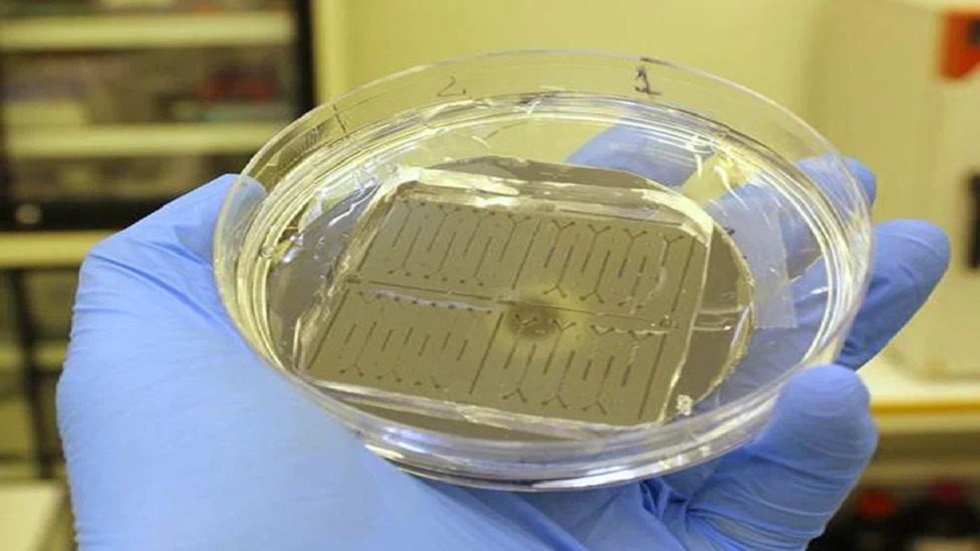

وقد ابتكر العلماء الروس شريحة ميكروفلويدية - جهاز صغير، يمر اللومينول (مركب كيميائي صيغته C8H7N3O2 قادر على توليد ضيائية كيميائية) ومحلول يحتوي على أنواع الأكسجين التفاعلية عبر قنوات دقيقة ذات بنية خاصة تعمل على تفتيت ومزج السوائل بسرعة فائقة. ثم يدخل اللومينول وأنواع الأكسجين التفاعلية إلى منطقة قياس التألق الضوئي. ويستغرق التفاعل نفسه جزءا من الثانية.